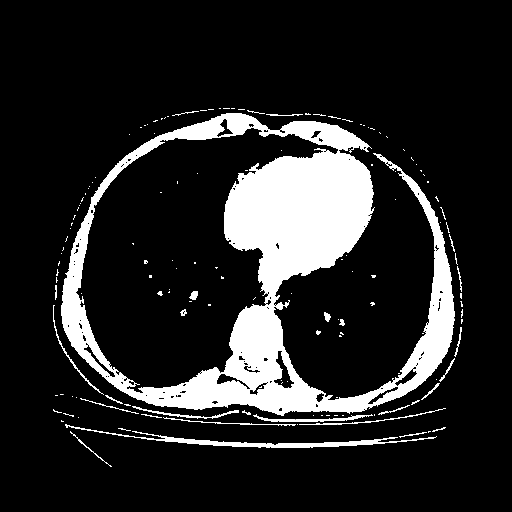

Image Grid

4Γ—3 grid: Rows show different image types (Original NATIVE, Reconstructed NATIVE, Original VENOUS, Generated VENOUS), Columns show windowing techniques (No Window, Lung Window, Mediastinum Window)

Generated VENOUS CT scan (A→B translation)

Full window (WL 1023.5, WW 4095 β†’ Low βˆ’1024, High +3071)

Actual HU range: [-1024.0, 3071.0]